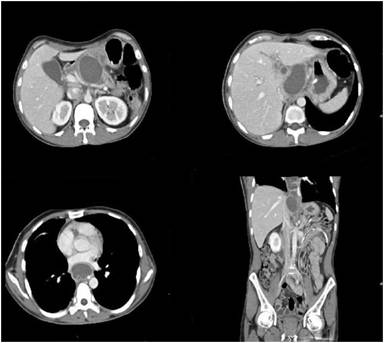

A forty five year old male, case of alcohol related chronic pancreatitis admitted with recurrent abdominal pain with dry cough. Chest X-ray showed massive right pleural effusion. Pleural fluid amylase was significantly elevated (67440 U/L). Intercostal drain was inserted to drain the pleural effusion. CT demonstrated features of calcific pancreatitis with ductal disruption in the body with pleuro-peritoneal and mediastinal fistulous tract along caudate lobe of liver (Figure 2).

Figure 2. Coronal CT reformat demonstrates a linear pancreatico -pleural fistulous tract along the caudate lobe of liver. |

The ductal disruption was localized to the superior body of pancreas. ERCP was attempted which showed disruption of the pancreatic duct in the body region, however the guide wire could not be negotiated into the ductal system and stenting was not successful. The patient was managed conservatively on nasoenteral feeds, intercostal tube drainage, injection octreotide and other supportive measures. During the hospital stay the patient developed persistent fever unresponsive to antibiotics. A repeat CT showed expansion of the pancreatico-mediastinal fistulous tract with large lobulated fluid collection along the pancreatic body which tracked through the esophageal hiatus into the posterior mediastinum (Figure 3). Ultrasound guided aspiration of collection was done which revealed frank purulent aspirate. This infected abdominothoracic collection was treated with percutaneous catheter drainage with placement of 10F pig tail catheter under ultrasound guidance, allowing complete drainage of the intra-abdominal and intrathoracic components of the pseudocyst over a period of approximately 1 week. The patient was also managed alongside with antibiotics and other supportive measures. The patient showed considerable improvement and was subsequently discharged. No separate treatment was thereafter required for the pancreatico-pleural fistula or ductal disruption. The total hospital stay was of 36 days. A follow up over approximately one year has not shown any recurrence of peripancreatic or chest collections. Recently the patient had a recurrent episode of acute exacerbation of pancreatitis involving body and tail region which was deemed to be of mild clinical severity and required a brief hospitalization.

Figure 3. Follow up CT in the above patient after few days of conservative management shows expansion of the fistulous tract with development of large collection along the tract extending into the mediastinum. |